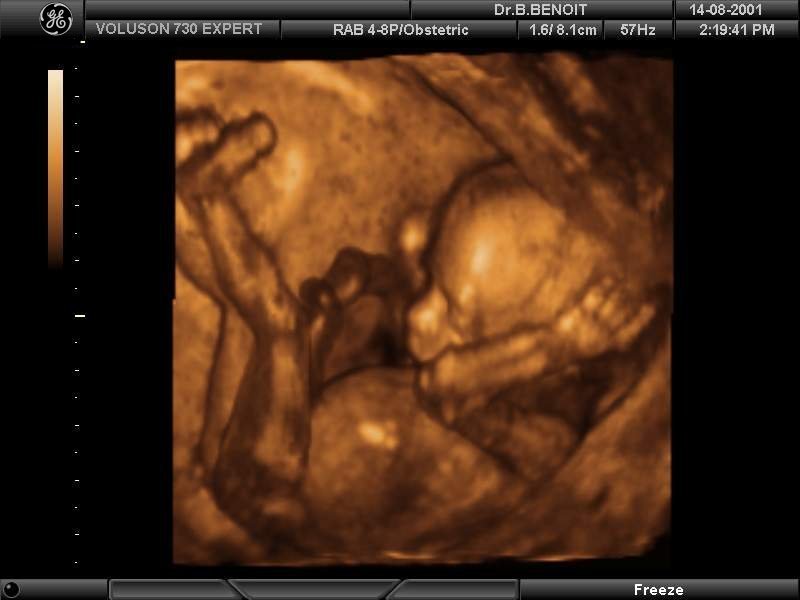

Ниже 16 недель беременности фото плода:

На 16-й неделе беременности ваш малыш по размеру сопоставим с авокадо, его длина составляет примерно 12,5-14 сантиметров, а вес колеблется от 130 до 150 граммов. Он (или она!) уже умеет сжимать кулачки и может начать сосать большой палец!

Сердечко вашего ребенка перекачивает около 23 литров крови в день. Пуповина полностью развилась и защищена специальным веществом, которое делает ее скользкой, что позволяет ей свободно двигаться вокруг малыша во время его активностей!

Вы, наконец, можете ощутить первые движения вашего ребенка, которые называются «ускорением». Эти ощущения могут напоминать легкие трепетания, газы или подергивания мышц, и иногда их можно принять за урчание в животе. Вскоре они станут более четкими ударами и могут даже мешать вам спать по ночам.

Ваш малыш также активно тренирует мышцы лица. У него начинают появляться волосы (привет, ресницы, брови и линия роста волос!), а на его прозрачной коже развиваются тонкие, мягкие волоски, известные как lanugo, которые помогают сохранять тепло в утробе. Глаза вашего ребенка, хотя и закрыты, начинают двигаться из стороны в сторону, и эти маленькие глазки могут даже начать улавливать свет.